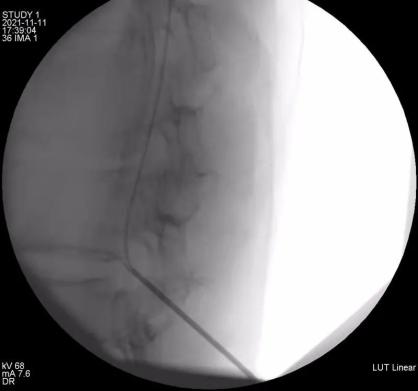

11月9日上午,余斌教授为还先生进行了镇痛泵安装前鞘内吗啡测试,结果显示鞘内吗啡对患者的镇痛效果十分明显。家属决定正式安装鞘内镇痛泵。11月11日下午,余斌教授经过仔细评估和精心准备后,会同新华医院马柯主任、同济医院骨科樊健主任、蔡涛医生一起,为还先生成功实施了该手术。术后镇痛效果良好,当晚还先生就没有了疼痛的折磨,VAS评分降至3分以下。自吗啡泵植入后,每天仅需吗啡0.4mg即可达到满意镇痛效果,阿片类药物副作用明显减少。解决了疼痛,患者的睡眠、饮食和精神状态都得到了极大的改善。

鞘内镇痛泵植入术

余斌教授介绍,鞘内镇痛泵植入术是通过微创手术,将一个可储存吗啡等镇痛药液的微量泵放置在皮下,并通过埋藏在皮下的导管将药液持续不断地输注到蛛网膜下腔,直接作用于中枢神经系统发挥镇痛作用。鞘内镇痛泵的用药量仅为静脉用药的1/100,口服药量的1/300,相比较其他的镇痛方式,其提高了镇痛效果,大大降低了药量,减少了药物不良反应,同时一次加药维持数月,方便长期控制疼痛,患者还可以根据自己疼痛程度自主调节用药剂量,体现了精准化医疗,舒适化医疗的理念。